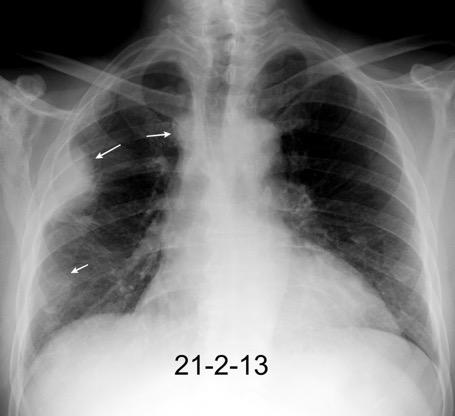

Marzo 2014: Perforación longitudinal distal secundaria a episodio de vómito (síndrome de Boerhaave). Derrame pleural izdo. que evoluciona a empiema.

Wang C-T et al. Tension hydropneumothorax in a Boerhaave syndrome patient: A case report . World J Emerg Med, 2021. Katabathina V et al. Nonvascular, nontraumatic mediastinal emergencies in adults:a comprehensive review of imaging findings. Radiographics. 2011.